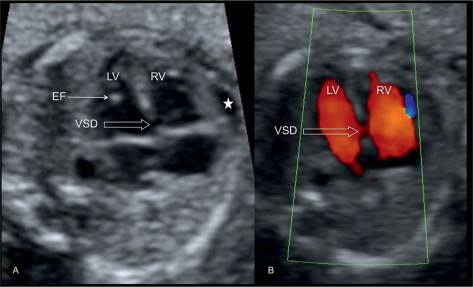

При скануванні ретельно оцінюються всі органі та системи: головний мозок, спинний мозок, обличчя, кістки, легені, діафрагма, серце, нирки, сечовий міхур, шлунок, кишечник, стінку живота, щоб діагностувати або виключити вроджені вади органів. Дослідження проводиться за допомогою кольорового та спектрального доплера, включно з ехокардіографією плода (УЗД серця плода).

При цьому також вимірюють розміри плоду та визначають його гестаційний вік і розвиток, оцінюють локалізацію, товщину та структуру плаценти, визначають кількость навколоплідної рідини, оцінюють довжину шийки матки. Дослідження триває 45 хвилин.